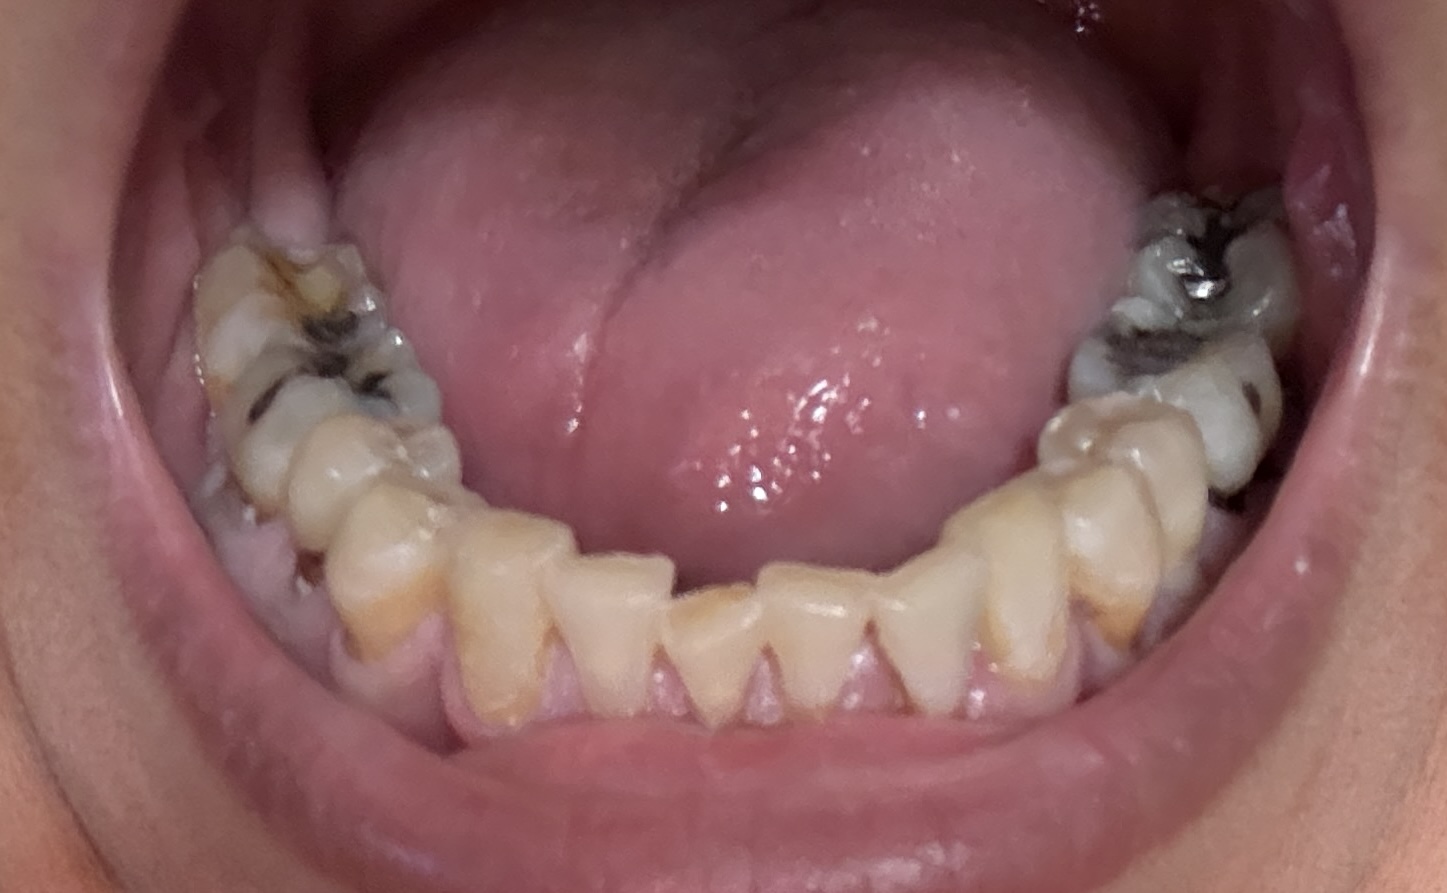

Overall information (lower arch)

Overall, all of my gums have receded and most of the bottom teeth are exposed w/ some roots and there are many cavities.